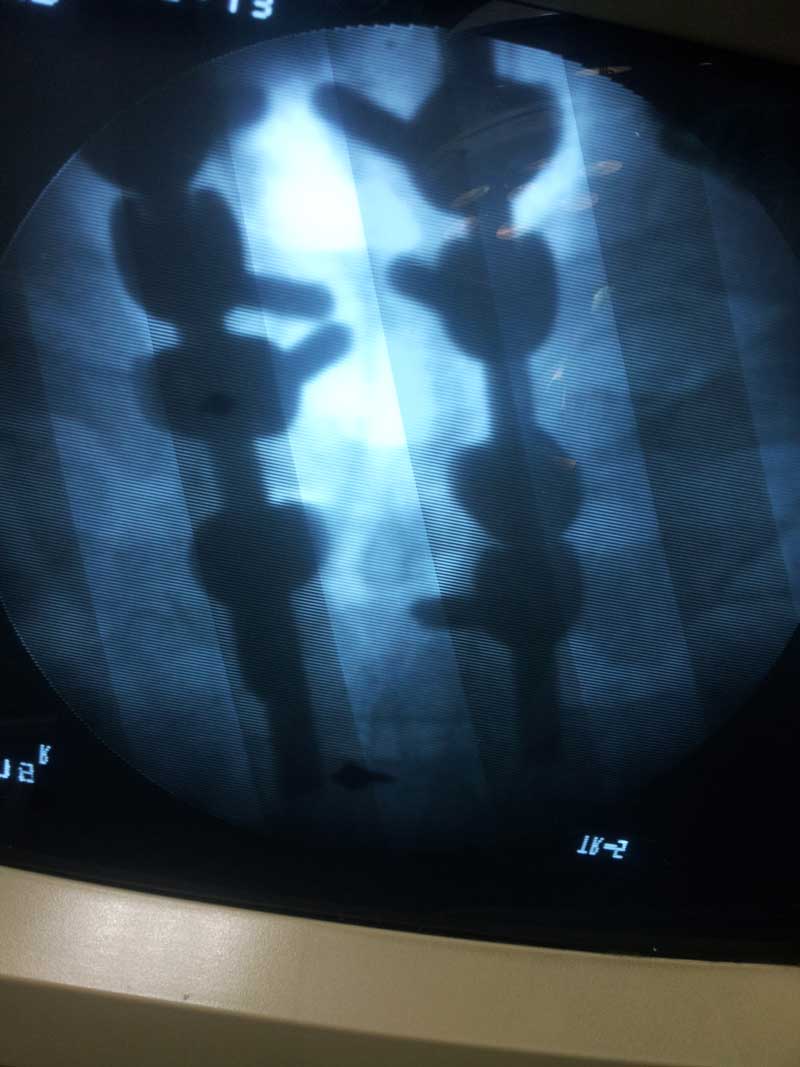

DORSAL SPINE FIXATION INTRA OP

Spine Fixation Lumbar Spine

• Spine Fixation Lumbar Spine